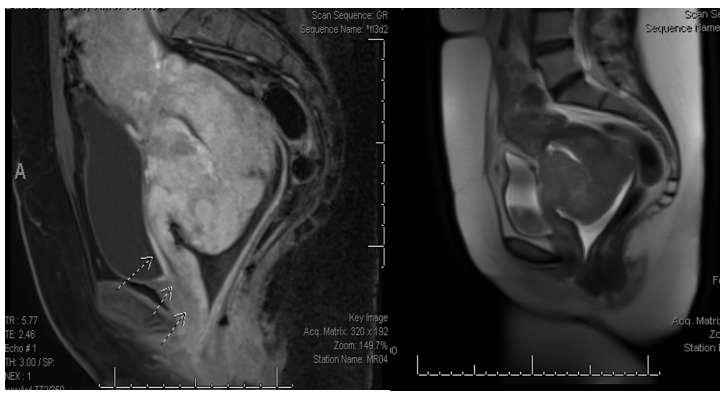

She had a computed tomography (CT) scan of the chest, abdomen and pelvis notable for large heterogeneously enhancing cervical mass, enlarged aortocaval lymph node, loss of fat plane between anterior wall of cervix and urinary bladder and 3.6 cm left adnexal cyst. Pelvic magnetic resonance imaging (MRI) demonstrated a large 9 cm multilobulated cervical mass with parametrial invasion and extension to the lower third of anterior vaginal wall, intimate association of posterior bladder wall with bullous edema, and enlarged left common iliac chain and bilateral external chain lymph nodes (Figure 1).

Figure 1 MRI pelvis with and without intravenous contrast at diagnosis.